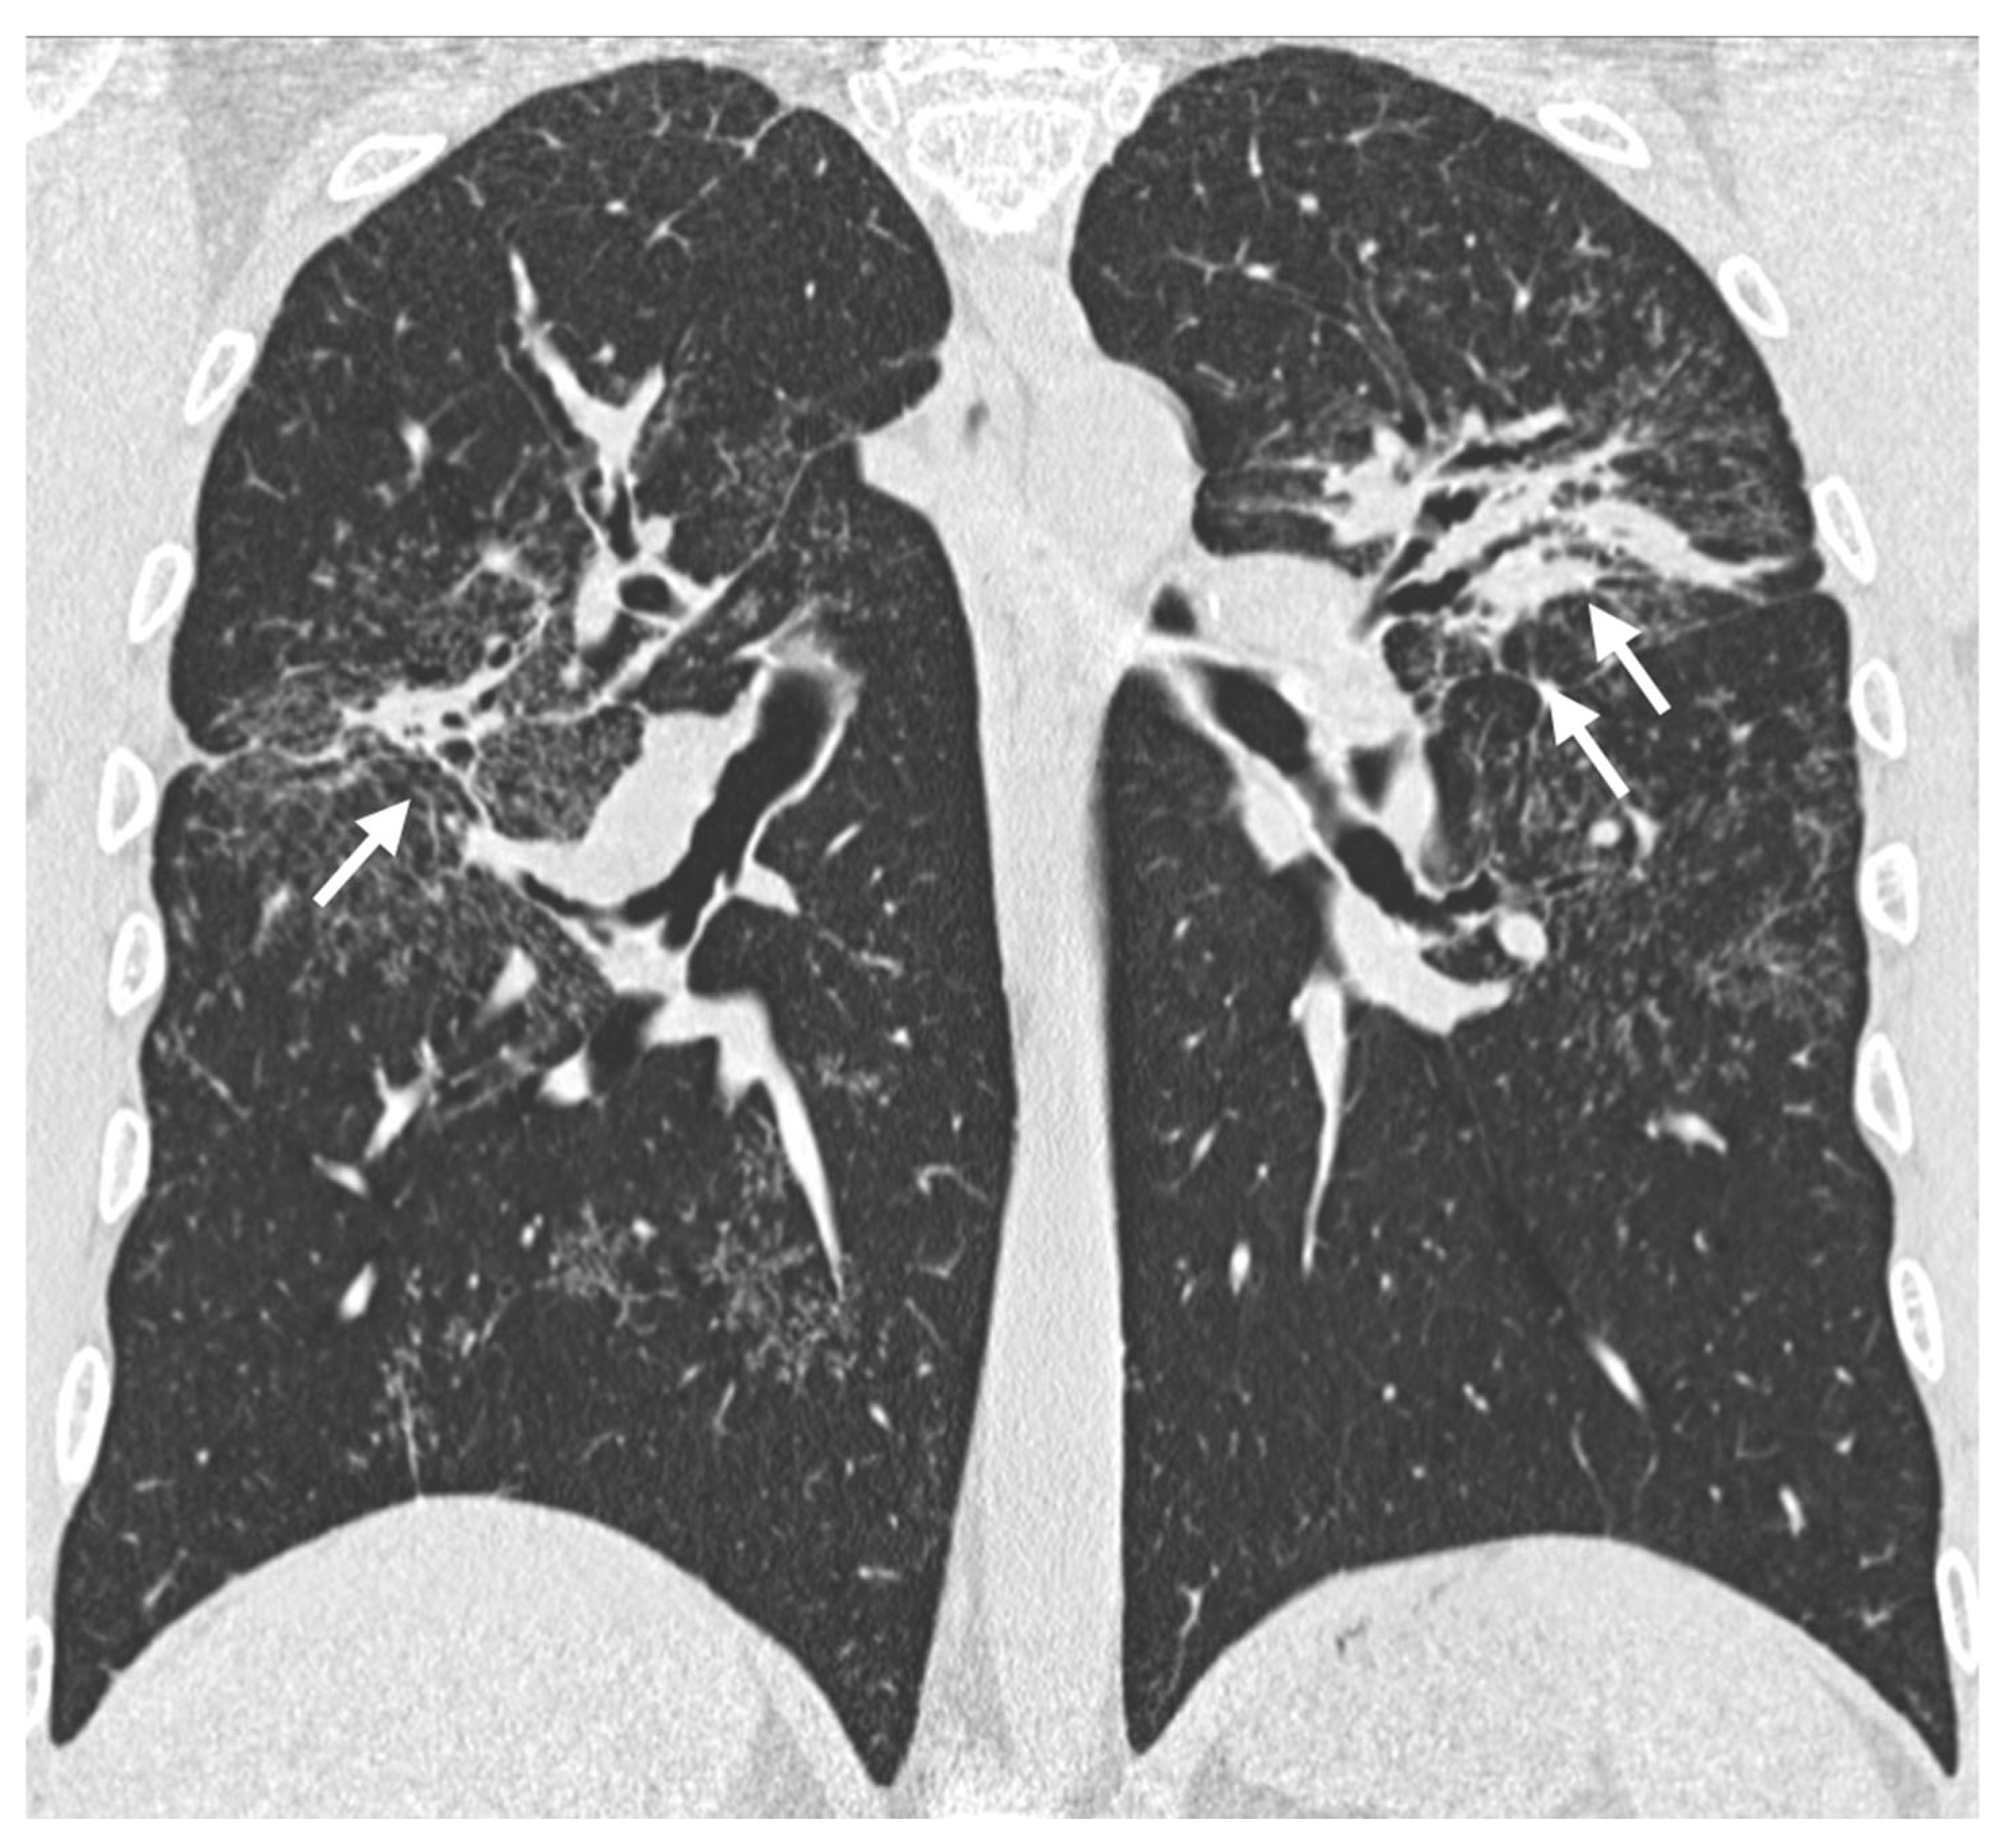

5. Fibrosis

5.1. Progressive Fibrosing Form

5.2. Association with Idiopathic Pulmonary Fibrosis

| Characteristic | Description |

|---|---|

| Incidence | Approximately 20% of patients with sarcoidosis |

| Origin | Chronic inflammation, long-lasting disease, or phenotypic susceptibility |

| Alterations | Linear opacities, traction bronchiectasis, architectural distortion |

| Distribution | Predominantly in the upper lobes and peribronchovascular regions |

| Honeycombing | Present in about 10% of patients, typically localized in middle-upper lobes |